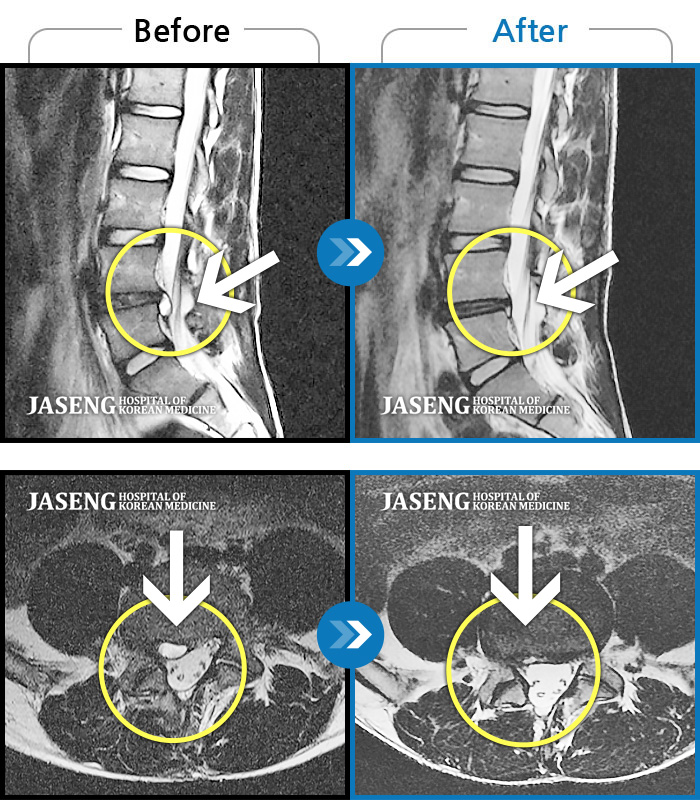

허리디스크

부천 · 신동재 원장

양쪽 허리와 골반 통증, 걸을 때 좌측 다리가 당기고 아픔

촬영시기

2016.01.12 ~ 2019.02.07

2019.02.27